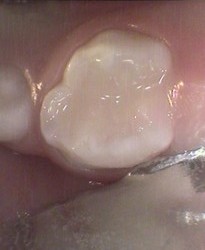

Unusual prevalent but superficial groove pattern on permenant molar after Sealed